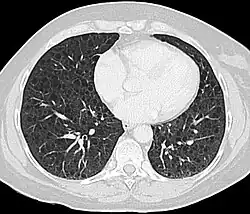

La LAM puede requerir atención médica de varias maneras, la mayoría de las cuales desencadenan una tomografía computarizada de tórax. Los cambios quísticos de paredes delgadas en los pulmones pueden encontrarse incidentalmente en tomografías computarizadas del corazón, el tórax o el abdomen (en los cortes que incluyen las bases pulmonares) obtenidas para otros fines. Las TCAR de pacientes con CET revelan que aproximadamente el 20 % de las mujeres presentan cambios quísticos a los 20 años y aproximadamente el 80 % de las mujeres presentan cambios quísticos después de los 40 años.[28] En ocasiones, la LAM se detecta mediante una TC de tórax en pacientes que presentan un neumotórax espontáneo primario aparente, pero con mayor frecuencia no se solicita la TC (en los Estados Unidos) hasta que se producen recurrencias. La disnea progresiva con el esfuerzo sin las exacerbaciones y remisiones que son características del asma o la EPOC a veces requieren una tomografía computarizada de tórax. Una revisión de la TC por un experto familiarizado con LAM puede aumentar la precisión del diagnóstico.[29] El quilotórax también puede llamar la atención sobre LAM.